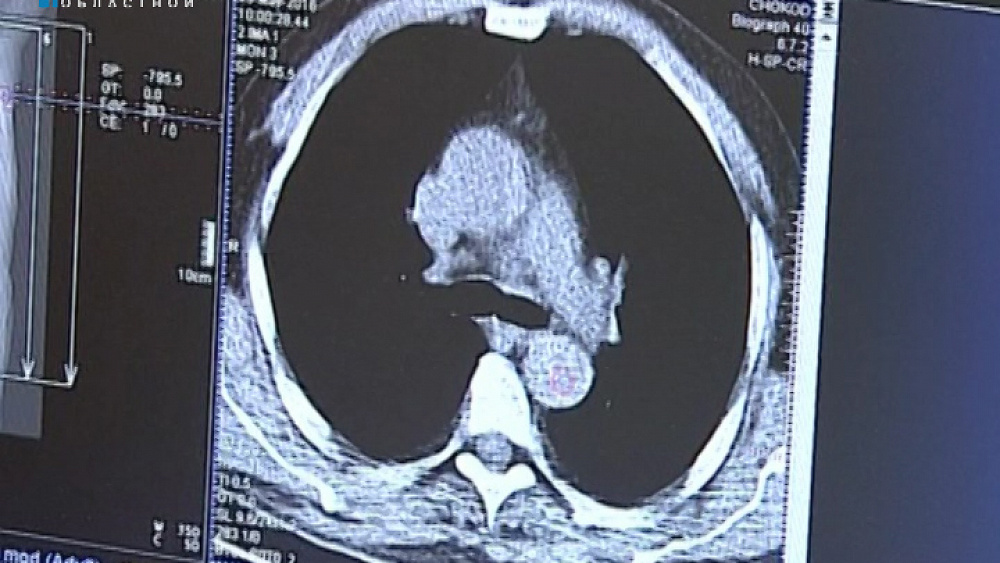

Диагностировать онкологию теперь будет отечественный препарат. Выпускают его в лаборатории Снежинска на отечественном оборудование. Новый "Циклон" - это аналог зарубежных аппаратов. Его создали в Петербурге. Аппарат позволит проводить больше обследований и на ранних стадиях выявлять злокачественные опухоли. Подробности у Ксении Кузнецовой